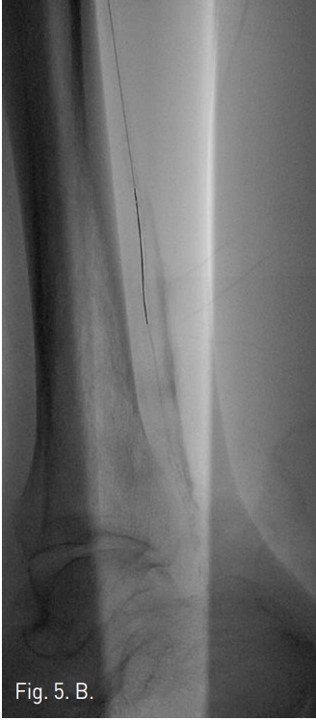

Fig. 5. B

B. The SV 5 Guide wire is passed through antegrade pathway.